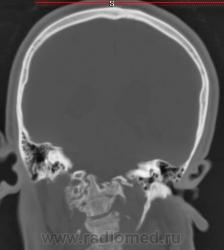

Nela. КТ головного мозга и костей. Гистиоцитоз Х (морфологическая верификация).

Пациент - молодой человек, предъявляет жалобы на головные боли и боли в шее. Болеет с 2002 года.

Гистиоцитоз Х – заболевание ретикулоцитарной системы неизвестной этиологии, морфологически характеризующееся первичной пролиферацией своеобразных гистиоцитов (клеток Лангерганса или клеток Х) и образованием в легких и в других органах и тканях гистиоцитарных гранулем и гранулематозных инфильтратов.

В понятие “гистиоцитоз Х” включают болезнь Abt–Letter–Siwe, болезнь Hand–Schuller–Christian, а также эозинофильную гранулему с разной степенью выраженности гистиоцитарной пролиферации.

Заболевание относится к системным: гранулемы могут образовываться в различных органах, но наиболее часто поражаются легкие и кости. Заболевают чаще всего люди молодого возраста, между 20 и 40 годами, большей частьюмужчины.